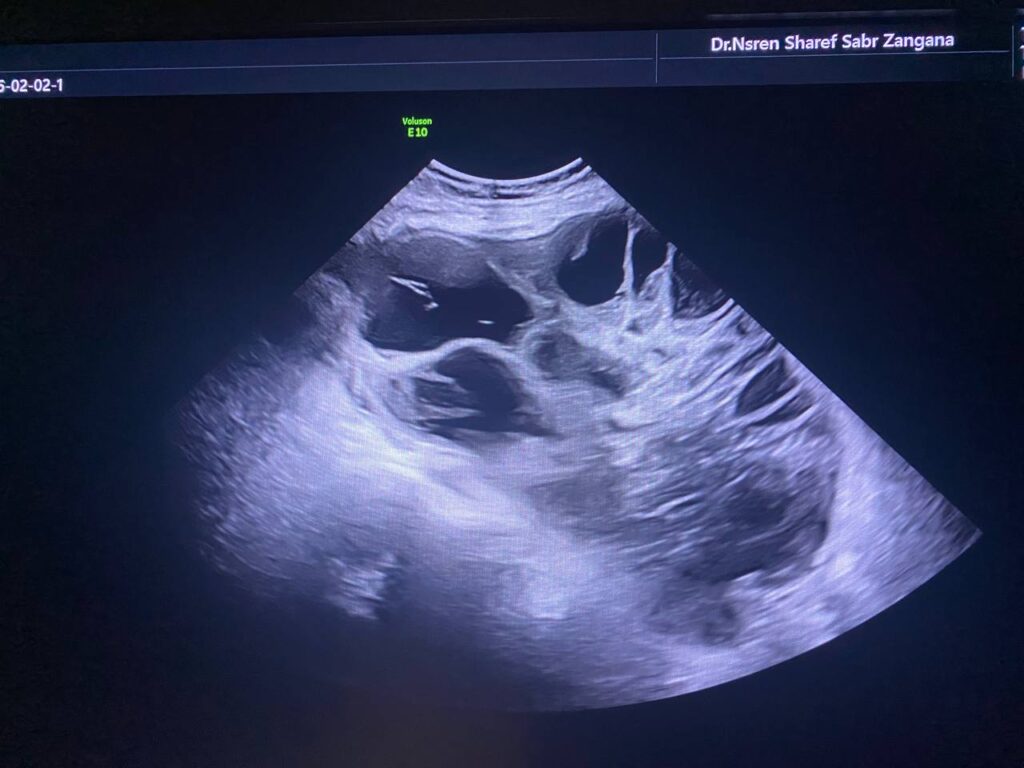

Right ovarian multilocular (>60 locules) solid mass , its size 170x140mm vascular on color doppler , color score 3-4 , with indistinct margins , associated with ascites , contains fine echoes , picture mostly of primary ovarian cancer ORADS 4 , no mass seen in the left ovary